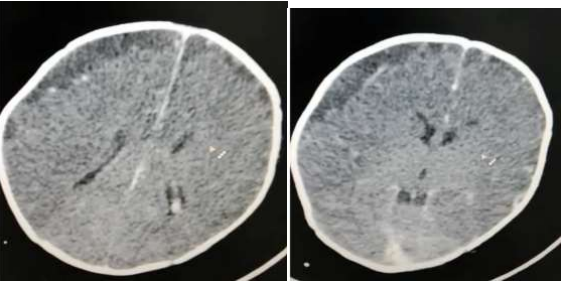

CT scan of the Head  as in Fig 1:Showing: right  frontal subdural  collection which  shows higher  density  than  cerebrospinal fluid CSF density  measuring 11 mm in  maximum  thickness  displacing the cortical  vein to the cortical outline with  adjacent leptomeningeal enhancement more than contra lateral side which could  represent infected  fluid /abscess or hygroma.

Generalized reduced attenuation of cerebral brain parenchyma with  less gray white  matter differentiation in  comparison to  the  cerebellum with  white cerebellar sine  which  could be  related to  reduced brain  parenchyma myelination at  this age

However hypoxic ischemic injury is another most likely possibility

Fig 1: CT Head Showing: right frontal subdural collection